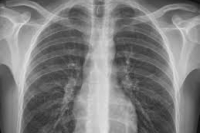

Рентгеновское обследование используется для создания изображений внутренних органов или костей, чтобы помочь диагностировать различные травмы. Специальная машина испускает (выдает) небольшое количество ионизирующего излучения, которое проходит через ваше тело и падает на пленку для получения изображения.

- Для диагностики состояния грудной клетки (например, пневмонии, рака легких, эмфиземы или сердечной недостаточности);